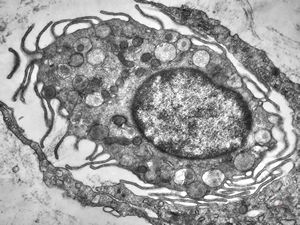

F, 24y. | molluscum contagiosum … virions

F, 24y. | molluscum contagiosum

F, 24y. | molluscum contagiosum

F, 7y. | molluscum contagiosum … virions

F, 7y. | molluscum contagiosum … virions

F, 24y. | molluscum contagiosum … virions